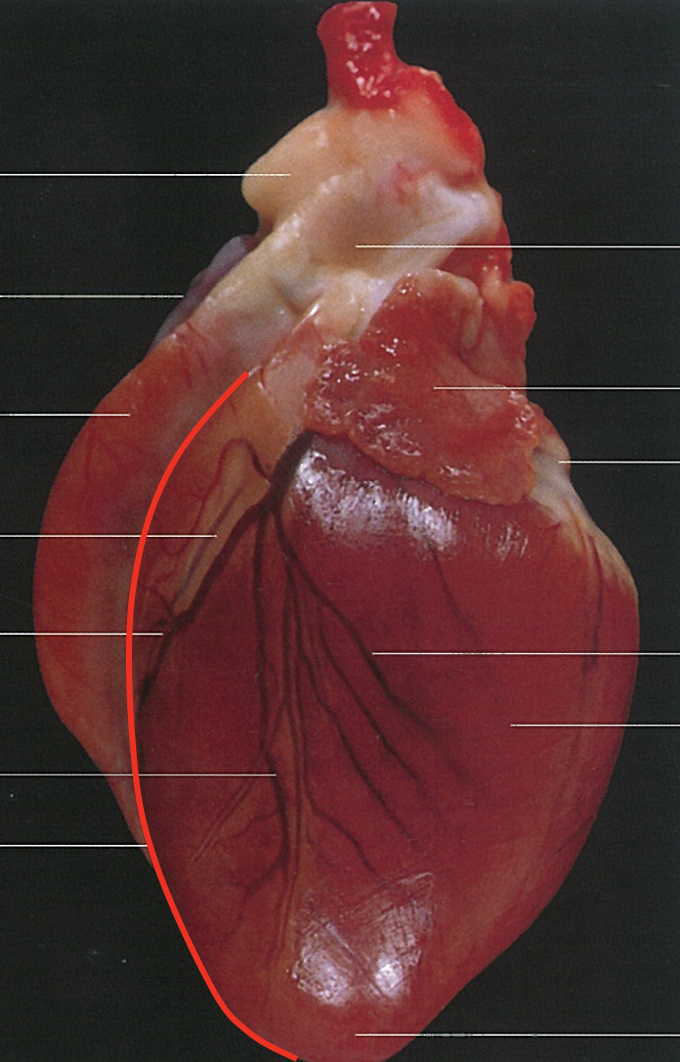

Name the Surface.

Auricular Surface

Apex

Paraconal Interventricular Groove

Name the surface

Atrial Surface

Subsinous interventricular groove

Notch of the Cardiac Apex

Coronary Groove

Vessels contained in the subsinous interventricular groove

* Terminal branch of left coronary artery * Middle coronary vein

Vessels contained in the paraconal interventricular groove

* Paraconal interventricular branch of the left coronary artery * Great coronary vein